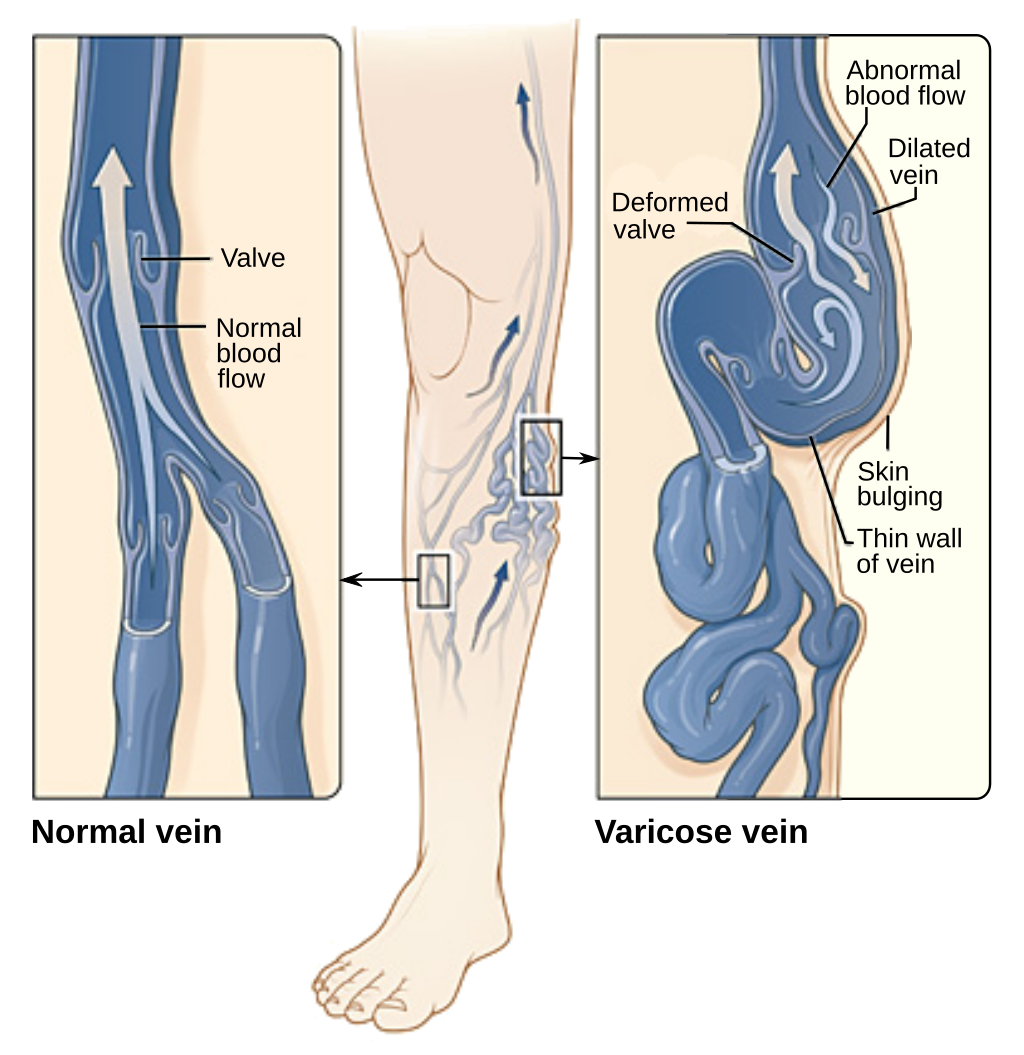

The thing is when deoxygenated blood accumulatein varicose veins, the pressure in veins increases and osmotic pressuredifference between vein wall and the surroundings allows the plasma to move outof the vein.When this happens lymphatic fluid also likely to sneak in surrounding tissue.

And due tothis lymphatic fluid and plasma with some RBCs in surrounding tissue it is soeasy for parasites to invade and infection take place.